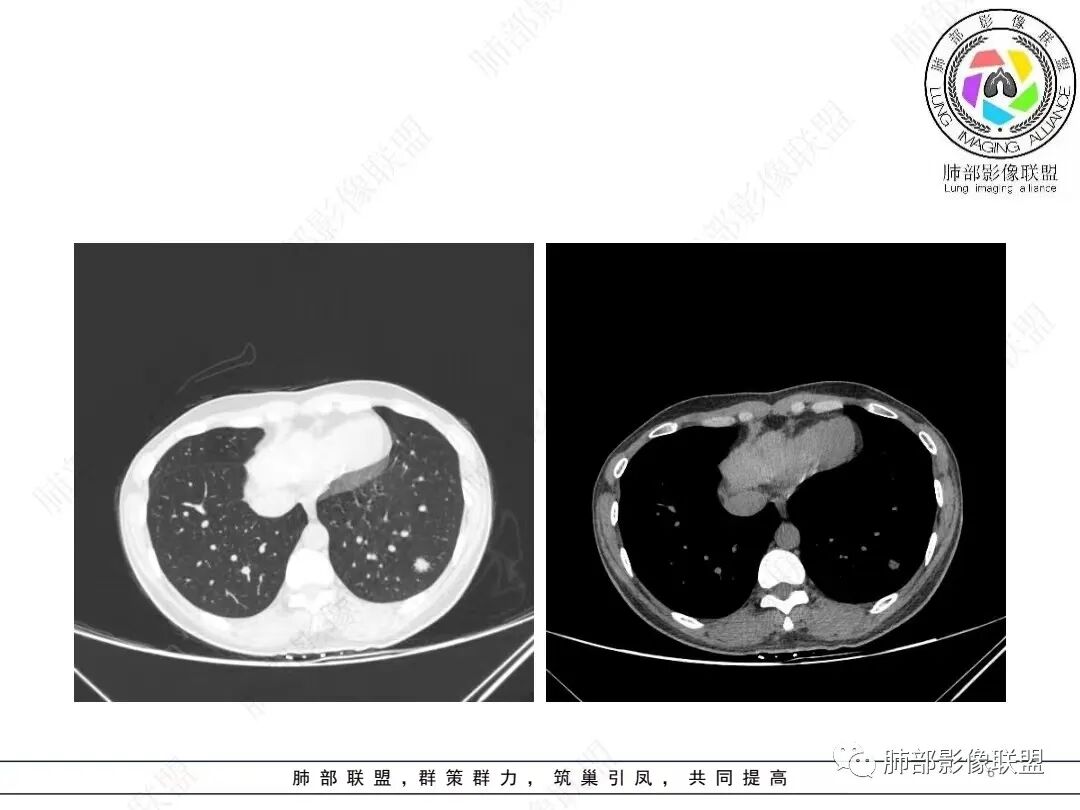

2、影像特点:左肺下叶类圆形结节影,周围可见多发细小毛刺,浅分叶,张力不高,未见胸膜牵拉。病灶内隐约见空泡影(未提供CT值),近端部分血管呈杵状增粗,可疑脐凹征。增强后实性部分有轻度强化。外围病灶,与支气管关系不明确。

年轻女性,体检发现,左肺下叶亚实性结节,边缘有毛刺、分叶,磨玻璃晕,病灶内可见裂隙样空腔改变,纵隔窗显示实性小于肺窗,近端血管呈杵状增粗,考虑腺癌,鉴别炎性结节(隐球菌),转移性结节。

左肺下叶后基底段实性结节,边缘锯齿状,实性强化明显,内见空泡征,见血管进入,首先肺腺ca。